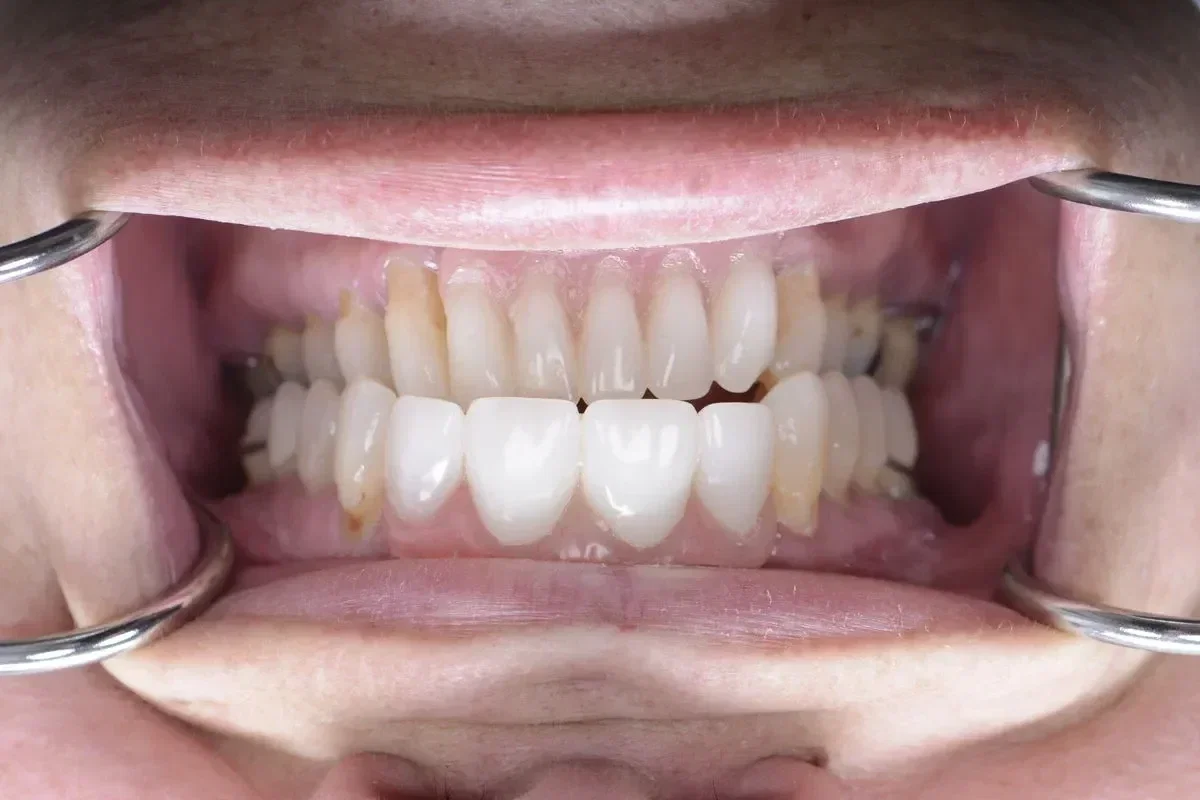

Real Smile Transformations

See the life-changing results from real patients who chose Fusion Dental Implants.

Our practice is built around the full arch restoration, including All-on-4, All-on-6, and zygomatic implant procedures. These treatments replace an entire arch of missing or failing teeth with a fixed, permanent set of new teeth supported by as few as four dental implants. Many of our patients receive temporary teeth on the same day as their surgery, leaving our office with a complete smile.